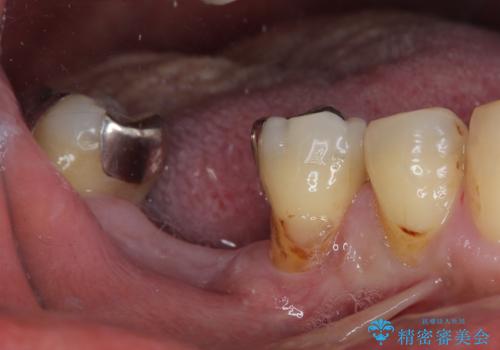

- 奥歯を抜歯してから放置しているとのことで来院された患者様です。

歯が割れて抜歯になってしまったとのことで、咬合力に抵抗できるよう、インプラントによる補綴治療を行うこととしました。

むし歯の放置期間と抜歯してからの放置期間が長く、咬み合わせる上顎の歯がやや伸び出している状態でした。

上顎の部分矯正や対合歯の補綴治療も提案しましたが、今回は欠損部のみの治療を行いました。